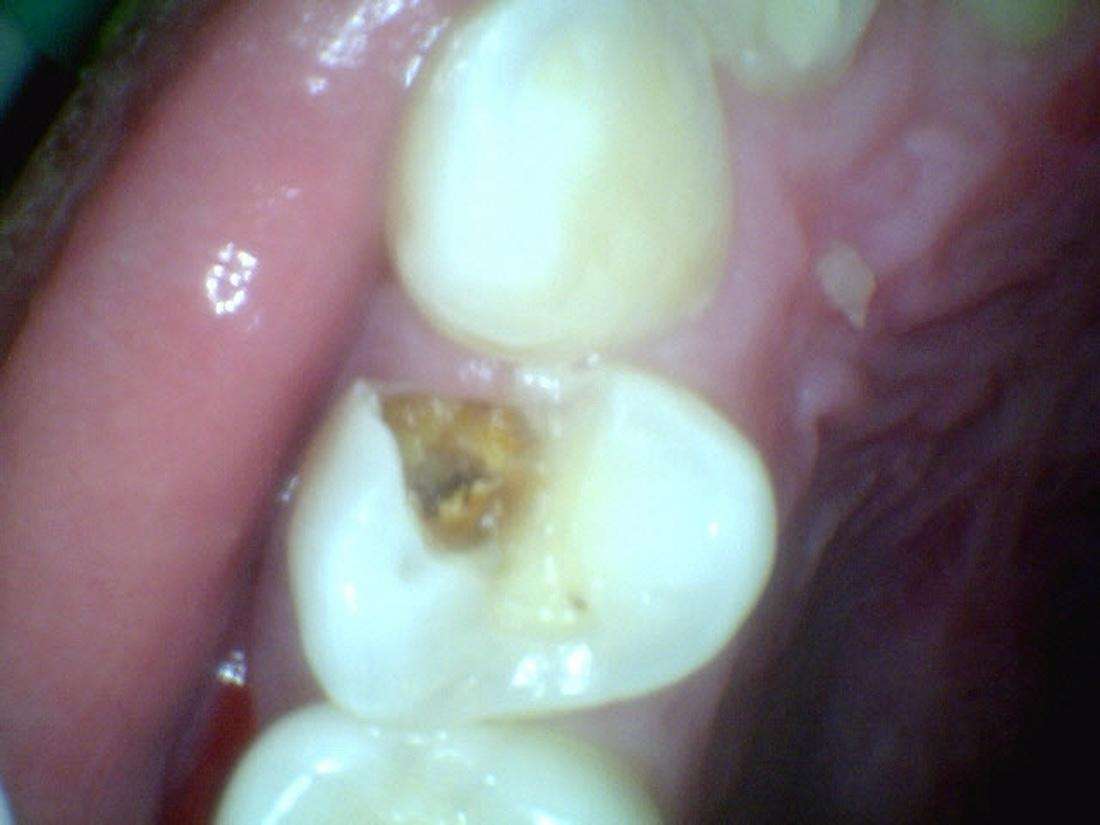

Fillings

Before

After